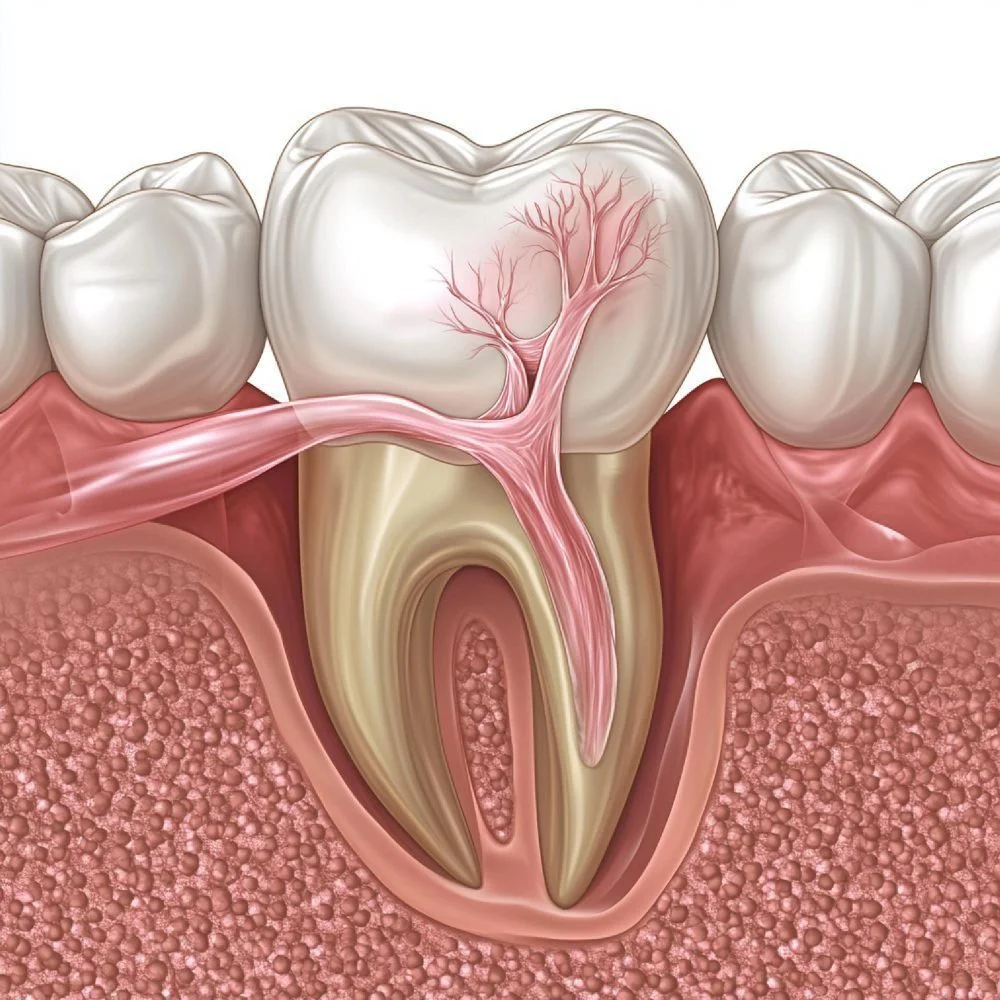

ما هو علاج أمراض اللثة؟

تُعد أمراض اللثة من أكثر مشكلات صحة الفم شيوعًا، ويمكن أن تؤدي إلى فقدان الأسنان إذا لم تُعالج في الوقت المناسب. في عيادتنا في سوريا – حلب، نقدم حلولًا متقدمة لعلاج أمراض اللثة والنسج الداعمة باستخدام أحدث التقنيات لضمان صحة لثتك والحفاظ على أسنانك الطبيعية.

نقدم علاجات متكاملة للوقاية من التهاب اللثة وعلاج التهاب دواعم السن المتقدم، بدءًا من التنظيف الاحترافي وصولًا إلى التدخلات الجراحية للحالات الشديدة.

يعتبر هذا الإجراء تنظيفًا عميقًا تحت خط اللثة لإزالة البكتيريا والجير المتراكم، مما يساهم في تحسين صحة اللثة ومنع تراجعها.

للحالات المتقدمة، نقدم جراحة الشقوق وتنظيف الجيوب العميقة وتجديد الأنسجة اللثوية باستخدام تقنيات حديثة لإصلاح الضرر الناتج عن أمراض اللثة.